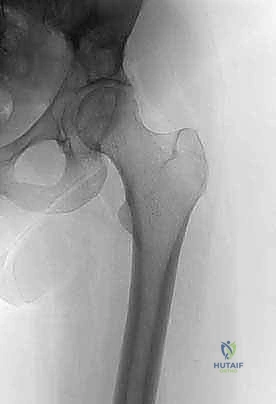

- التصوير بالأشعة السينية (X-rays): الفحص المبدئي لرصد أي تآكل أو تدمير في البنية العظمية للحوض ومفصل الورك.

التقييم البيوميكانيكي هو تخصص دقيق. يستخدم الدكتور هطيف معايير علمية (مثل معايير هارينغتون Harrington Criteria) لتحديد ما إذا كان عظم الحُق أو الحوض على وشك الانهيار.

* الكسر المرضي الفعلي: إذا انكسر الحوض بالفعل، فإن الجراحة ضرورية لتثبيت العظم المكسور والسماح للمريض بالحركة.

* الكسر الوشيك: إذا أظهرت الأشعة المقطعية أن الورم قد دمر أكثر من 50% من قشرة العظم المحيطة بمفصل الورك، أو تسبب في ألم شديد عند تحميل الوزن، فإن التدخل الاستباقي لمنع الكسر أسهل وأكثر نجاحاً من محاولة إصلاح كسر قد حدث بالفعل.